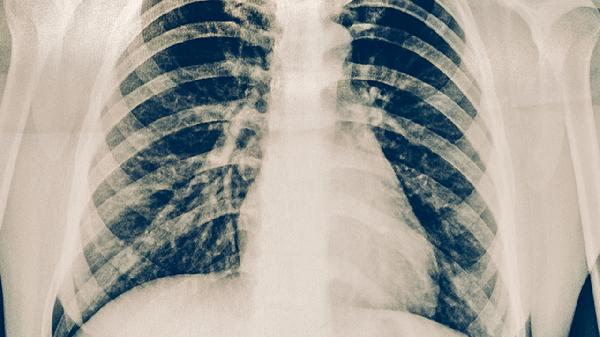

肋骨骨折了晚上睡觉疼得厉害怎么办

肋骨骨折夜间疼痛明显可通过药物镇痛、体位调整、呼吸训练、物理治疗、心理疏导等方式缓解。肋骨骨折多由外力撞击、骨质疏松、剧烈咳嗽等因素引起,疼痛程度与骨折数量、位置及个人耐受性相关。

肋骨骨折恢复期需保持高蛋白饮食促进骨痂形成,每日摄入牛奶、鱼肉等优质蛋白。避免剧烈咳嗽及突然转身动作,睡眠时使用多个枕头支撑体位。定期复查X线观察愈合进度,若出现呼吸困难、发热等症状需立即就医。一般单根骨折需4-6周愈合,多根骨折可能延长至8-12周,老年患者或骨质疏松者恢复时间更长。